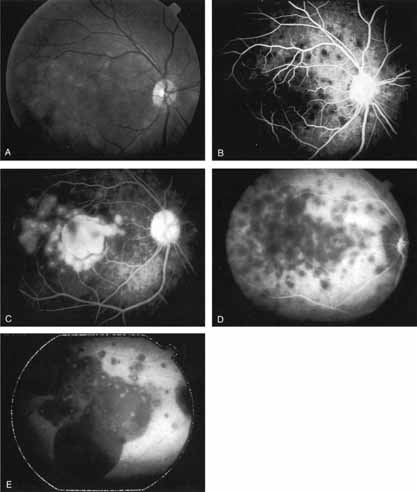

Harada disease, an inflammatory condition often affecting both eyes in young patients, is typified on fluorescein angiography by multiple focal areas of hypofluorescence early in the study, followed by late confluent leakage in the later phases (Fig. 17A, 17B, and 17C). With ICG angiography, multiple focal hypofluorescent spots are seen in the early phases, many more than were noted on the fluorescein study64,68 (Fig. 17D). The process extends further than the clinically or angiographically involved areas. The spots vary in size and density but appear to be well circumscribed. In the later phases of the ICG study, there is generalized hypofluorescence, with masking of the background choroidal fluorescence by the neurosensory detachment (Fig. 17E). This masking effect covers a large area, with inferior round margins confirming the gravitating nature of the neurosensory elevation. In addition, focal hyperfluorescent spots can be seen, possibly representing sites of active chorioretinal leakage or inflammation. In one patient, steroid therapy resulted in a marked resolution of clinical findings within 1 week.68 Repeat ICG angiography revealed a marked resolution of the hypofluorescent lesions as well as the hyperfluorescent spots. New areas of hypofluorescence did appear, the significance of which remains undetermined (Fig. 17E). |